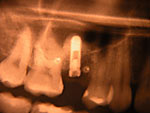

Implantation – Patientenbeispiel 1: